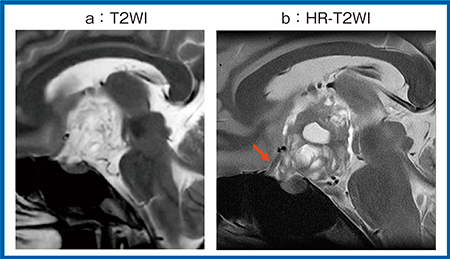

ZGOで使用可能なDLRは,同一データセットの低SNRな入力画像と高SNRな教師画像を畳み込みニューラルネットワーク(CNN)を構築して学習させ,これを画像再構成の流れに組み込んでデノイズ(ノイズ除去)に応用した技術である。DLRは最適なデノイズ強度を選択する必要があるが,自動でノイズ計測を行い最適なデノイズ強度を設定する機能を有しているため,臨床で使用しやすい。症例1(図1)は頭蓋咽頭腫であるが,ルーチンのT2強調画像(T2WI)(a)と比較して,DLR処理後のHR-T2WI(b)では腫瘍性の病変が視神経を押し上げている様子がより明瞭に確認でき(→),周囲の構造との位置関係も把握しやすい。

図1 症例1:頭蓋咽頭腫におけるHR-T2WIの有用性